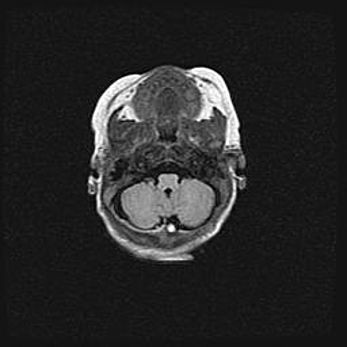

Сообщающаяся гидроцефалия. Кистозная энцефаломаляция головного мозга.

Возраст: 3 месяца 4 дня

Вес: 3100 г

Пол: женский

Окружность головы: 34 см

Срок гестации: 31 неделя

Кистозная энцефаломаляция головного мозга - одна из форм поражения головного мозга в детском возрасте. Характеризуется возникновением множественных и распространённых кист в коре, белом веществе и подкорковых образованиях головного мозга у плодов, новорождённых и детей раннего возраста. Развитие кистозной энцефаломаляции связано с внутриутробной асфиксией и гипотонией, родовой травмой, тромбозом синусов, пороками развития сосудов, инфекциями, сепсисом и другими причинами. Наиболее значимые инфекционные агенты: вирусы простого герпеса, цитомегалии, краснухи, токсоплазмы, энтеробактерии, золотистый стафилококк и другие.